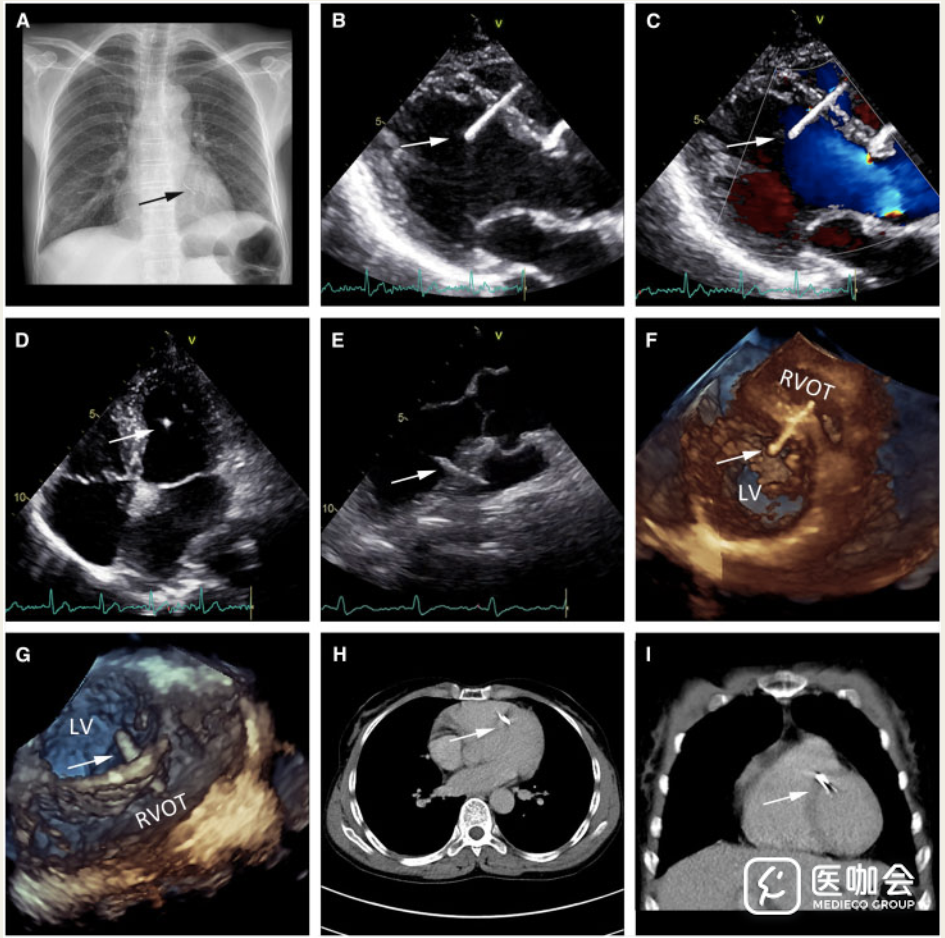

患者,女,55岁,因阵发性右上腹痛就诊,被诊断为胆结石。术前胸片显示心脏有致密条状阴影(下图A)。经胸和食管超声心动图证实致密条状阴影是异物(27毫米长),从右上到左下穿透室间隔,无室间分流。非增强CT显示在右心室和左心室以及室间隔(下图H和I)有异物。

医生推测绣花针从右心室流出道斜穿至室间隔前部,部分进入左心室。目前不需要手术去除,因为针头已经内皮化,并没有造成心脏的结构性损伤。需要定期进行超声心动图检查,以确保该异物不会对患者造成进一步的心脏损伤。